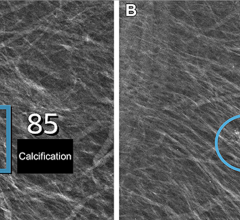

June 5, 2024 — Nano-X Imaging, an innovative medical imaging technology company, today announced that its deep-learning ...

June 4, 2024 — Using artificial intelligence (AI), breast radiologists in Denmark have improved breast cancer screening ...

May 28, 2024 — iCAD, Inc., a global leader in clinically proven AI-powered cancer detection solutions, announced a ...